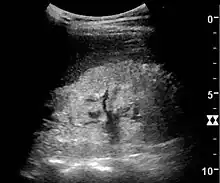

Ultrasound

Kidney ultrasonography is useful for diagnostic and prognostic purposes in chronic kidney disease. Whether the underlying pathologic change is glomerular sclerosis, tubular atrophy, interstitial fibrosis, or inflammation, the result is often increased echogenicity of the cortex. The echogenicity of the kidney should be related to the echogenicity of the liver or the spleen. Moreover, decreased kidney size and cortical thinning are often seen especially when the disease progresses. However, kidney size correlates to height, and short persons tend to have small kidneys; thus, kidney size as the only parameter is unreliable.[59]

Chronic renal disease caused by glomerulonephritis with increased echogenicity and reduced cortical thickness. Measurement of kidney length on the US image is illustrated by '+' and a dashed line.[59]